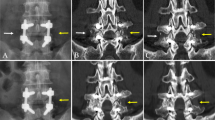

Follow-up was done on patients radiologically at 3, 6, 12 and 18 months after surgery. The fusion success evaluation was based on findings on the 12-month plain radiographs. Radiographic assessment of the fusion was based mainly on anteroposterior and flexion-extension dynamic plain radiographs because not every patient would consent to computerized tomography (CT) scans. Fusion criteria described by Christensen et al. were applied to evaluate all plain radiographs [11]. The fusion mass should be visible laterally to the instrumentation and at the intertransverse fusion areas. A successful fusion was determined as continuously qualitative intertransverse bony bridging at the target level on the follow-up radiographs (Fig. 1). Suboptimal quality or a fusion mass hidden by the instruments is considered as unsuccessful fusion (Fig. 2).

Radiographs from left to right showed the immediately, 3, 6, and 12 months postoperatively. The immediately postoperative image showed multiple opacity spots at the intertransverse space indicated a mixture of hydroxyapatite-β-tricalcium phosphate granules with laminectomy bone chips and DBM. The 12-month image showed a successful fusion mass with continuously qualitative bony bridging at the intertransverse fusion areas

Radiographs from left to right showed the immediately, 3, 6, and 12 months postoperatively. The immediately postoperative image showed bone graft materials (tricalcium phosphate granules, laminectomy bone chips and DBM) at the intertransverse space. The subsequent images showed absorption of the bone graft materials and unsuccessful fusion mass formation